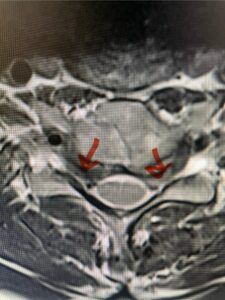

In this next case, this patient is a 47 year-old female who presents with intractable low back pain with severe pain, numbness, and weakness in the right lower extremity that had gotten progressively worse over a year. The patient had failed conservative management including physical therapy and epidurals. She was noted to have ⅘ weakness of plantar flexion. MRI demonstrated a large right L5-S1 disc herniation with severe compression of the descending right S1 nerve root (Fig 3). It was decided to perform a right L5-S1 hemilaminectomy for removal of the disc fragment and decompress the S1 nerve root. When you expose the disc, one must be certain to release any anterior adhesions to the nerve root in order to prevent a dural tear during retraction of the nerve root. It is also important to make sure during exposure and you finally encounter the dura after removing the ligamentum and fat, to make sure you are looking at the nerve root and not the main trunk of the thecal sac because if you don’t you can avulse or damage the nerve root if you retract the wrong structure.

Fig. 3a: Sagittal and axial T2-weighted lumbar MRI images demonstrating large right L5-S1 disc herniation (red arrows)

We found a massive subligamentous herniation which had to be revealed by having your partner retract the freed nerve root with a nerve root retractor and putting slight downward pressure on the more medial and anterior disc space. There is nothing more satisfying when the jelly (disc fragment) of the annulus (donut) comes squirting out and you remove a large chunk of disc material that clearly was stretching the ligament membrane and compressing the nerve root. This does cause back pain in addition to radiculopathy not only by the component of mechanical compression but also the stretching of the nerves within the ligament. We performed this surgery and noted that the nerve root was a very angry red color or hyperemic and we removed a large subligamentous fragment. The patient had improvement of her preoperative radicular symptoms.